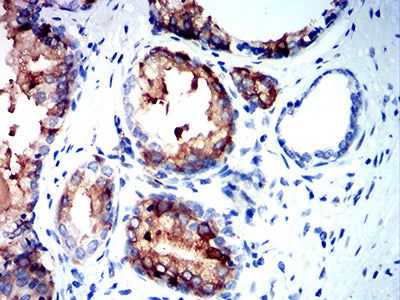

分类: 科研抗体货号: 31890别名: MLP; SMUC; MUC-2应用: IHC,FCM反应种属: Human,Mouse,Rat,Rabbit

鄂公网安备42018502007531号